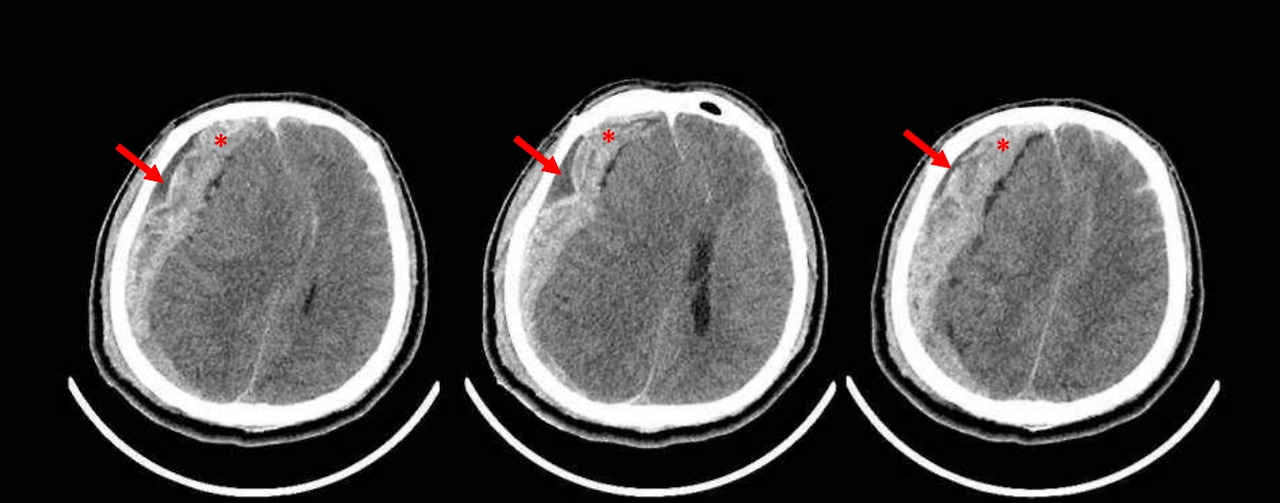

서울대병원 응급실에 백남기 농민이 이송됐다. 경찰의 물대포를 머리에 맞고 넘어진 백 농민은 의식을 잃은 상태였다. 당시 의무기록에는 글래스고우 혼수계수(Glasgow coma scale)가 3점으로, 최고 중증 상태의 혼수(coma)였고 생명을 유지시켜주는 기본 기능을 담당하는 뇌줄기 반사도 없었다. 뇌단층촬영검사(Brain CT)에서는 다발성 두개골 골절과 엄청난 량의 급성경막하출혈, 그리고 긴급한 응급처치를 요하는 뇌탈출증이 발견됐다.

최초 뇌단층촬영검사(CT)를 토대로 백 농민의 외상 기전은 이렇다. 우측 두정골 부위 두피에 부종이 있는 것은 이 부위에 직접적 외상이 가해졌다는 것을 의미했다. 우측 머리덮개뼈(두정골, 측두골, 후두골)과 얼굴뼈(접형골, 광대골)의 골절은 물대포에 의한 직접적인 충격 또는 우측 머리가 바닥에 충돌하면서 생긴 외상이었다.

양측 광대골절이 접합부에서 대칭적으로 형성되어 있고, 골절 부위에 뼈의 어긋남이 없으며, 골절 부위에 연조직 부종도 없는 점을 고려하면 이 부위에 직접적인 충격이 가해져 골절이 발생했을 가능성이 낮았다. 따라서 양측 광대활의 골절은 심한 외상에 의해 발생하는 두개골 기저부 골절과 연관되어 발생했을 가능성이 높았다. 우측 안와골절의 원인은 눈 부위의 직접적인 충격 때문이 아닌 두개골 기저부가 골절되면서 기저부를 이루는 접형골이 골절되어 발생한 것이다.

수술 후 13번의 CT 촬영결과는 지속적으로 백 농민의 상태가 악화되고 있음을 나타냈다. 수술 후 뇌경색이 발생했고, 뇌부종과 뇌탈출증이 호전되지 않았다. 또 뇌 전체에서 뇌손상에 의한 뇌연화증이 진행되고 있었다.